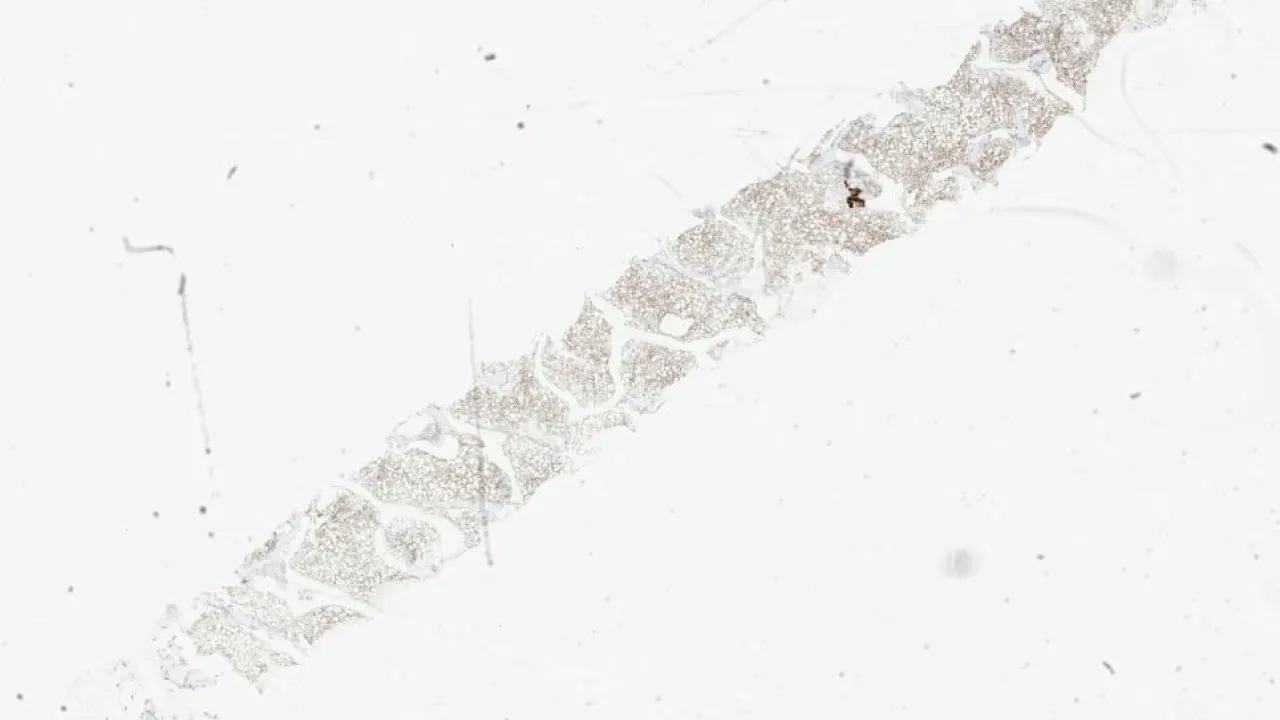

Lymph Nodes, Mantle cell lymphoma, CD23 stain